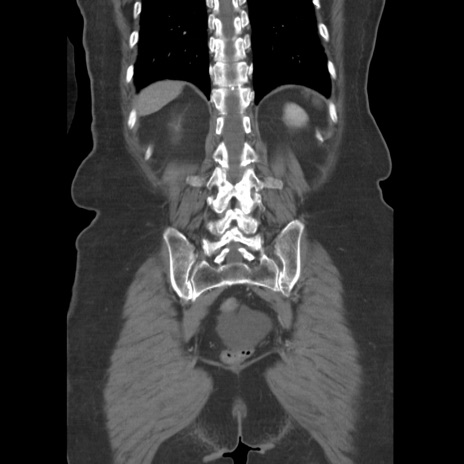

症例19(冠状断像)

【症例】80歳代女性

【主訴】下腹部痛

【現病歴】約8時間前より下腹部痛の出現あり、救急外来受診。

【既往歴】両側付属器切除

【身体所見】意識清明、下腹部正中に手術痕あり、その部位に一致して圧痛と反跳痛あり。腸蠕動音は亢進。

【データ】WBC 9300、CRP 0.15